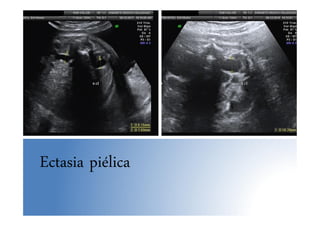

• Ectasia piélica: >7mm en 3º T. Control eco sem. 36-37

Ectasia piélica

Anomalías nefrourológicas • Examenecográfico: – Vejiga: arterias umbilicales a ambos lados, en 3º T se llena y vacía +/- cada 30 min. – Riñones: • Medida de pelvis renales en un corte transversal, a partir de la semana 33 el punto de corte para el Dx de ectasia piélica se sitúa en 7 mm. en sentido AP in to in • En 3º trimestre: borde ecogénico (grasa perirrenal), diferenciación corteza, pirámides y pelvis • Medida del riñón: EG + 10 mm

Anomalías nefrourológicas • Uropatíasobstructivas – Son el 75% de las anomalías nefrourológicas Dx prenatalmente – Más frecuente en varones 5:1 – Tasa de resolución espontánea elevada (40%) – La más frecuente la dilatación ureteropiélica • Ectasia piélica: >7mm en 3º T. Control eco sem. 36-37 • Hidronefrosis: > 10 mm. 4 grados. Imágenes eco(-) comunicadas entre sí, parénquima renal conservado o adelgazado, controles eco/4-6 sem., 80% manejo postnatal expectante • Doble sistema pielocalicial: aislado es una variante de la normalidad, muy frecuente, 2 pelvis separadas no comunicadas con duplicación parcial o completa de uréteres. Ureterocele frecuente